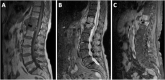

Query (Q) fever is a zoonotic bacterial infection caused by Coxiella burnetii. In a minority of patients, chronic disease can occur after acute infection. Endocarditis and infections of aneurysms or vascular prostheses are the most common forms of chronic Q fever in adults. We report a case of an elderly female patient with chronic Q fever vertebral osteomyelitis at the site of her previous cement vertebroplasty, complicated by paravertebral abscess. Patient treatment required prolonged drainage in addition to the long duration of antibiotic treatment by doxycycline and hydroxychloroquine. Osteomyelitis is a rare clinical presentation in adults with chronic Q fever. However, it is important to consider Q fever in the differential diagnosis of culture-negative osteomyelitis, especially in countries where C. burnetii is endemic, such as Israel.